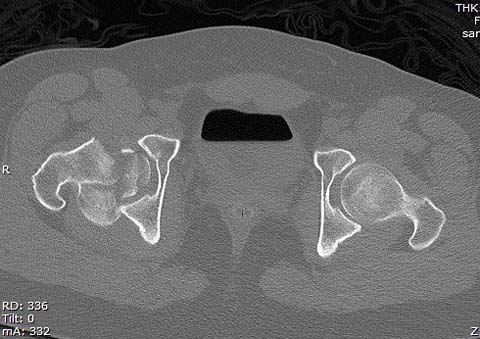

Уважаемые коллеги добрый вечер! Хотелось бы узнать ваше мнение о возможных ранних сроках наступления асептического некроза или коксартроза при данном виде оперативного лечения, может кто-то уже оперировал данную патологию и есть наблюдения. Случай практически идентичный описанный в январе 2015 на ортофоруме Никитой Николаевичем Заднепровским. Молодой человек 20 лет ДТП 23.02.2015, Диагноз: Сочетанная травма. Закрытый переломо-вывих головки и перелом заднего края вертлужной впадины (Pipkin4) правой бедренной кости. Открытый подтаранный вывих правой стопы. При поступлении в ЦРБ вправление вывиха головки бедра и подтаранного вывиха стопы.

Далее перевод к нам в Травмоцентр и 03.03.2015. через 8 дней операция, выполнен остеосинтез головки 3-мя самокомпрессирующими винтами Autofix под разными углами с погружением в субхондральный слой. Доступ Kocher-Langenbeck с флип-остеотомией большого вертела и задним хирургическим вывихом головки бедра. В полости сустава два свободно-лежачих фрагмента хряща головки, которые были удалены. На снимках виден дефект хряща головки после репозиции. Небольшой фрагмент заднего края фиксирован двумя спонгиозными винтами. Далее шов раны с дренированием. На 2 сутки пациент поворачивался на здоровый бок с валиком между ног, на 4 сутки сидел в кровати и на 6 сутки ходил с помощью костылей.

КТ после вправления - это последнее?

На мой взгляд, развитие артроза и AVN в большей степени зависит от давности вывиха и качества оперативной техники. Хирургический вывих бедра- не самая простая процедура и с подводными камнями, в остеосинтезе из переднего доступа тоже есть проблемы.

Здесь значимый задний край с подвывихом бедра кзади и острым краем вертлуги - задний доступ с вывихом и синтезом заднего края винтами и пластиной

Здесь клинические примеры: Первый случай передний доступ, второй с ICP monitor Flipp Trochanteris

и с переломом заднего края.